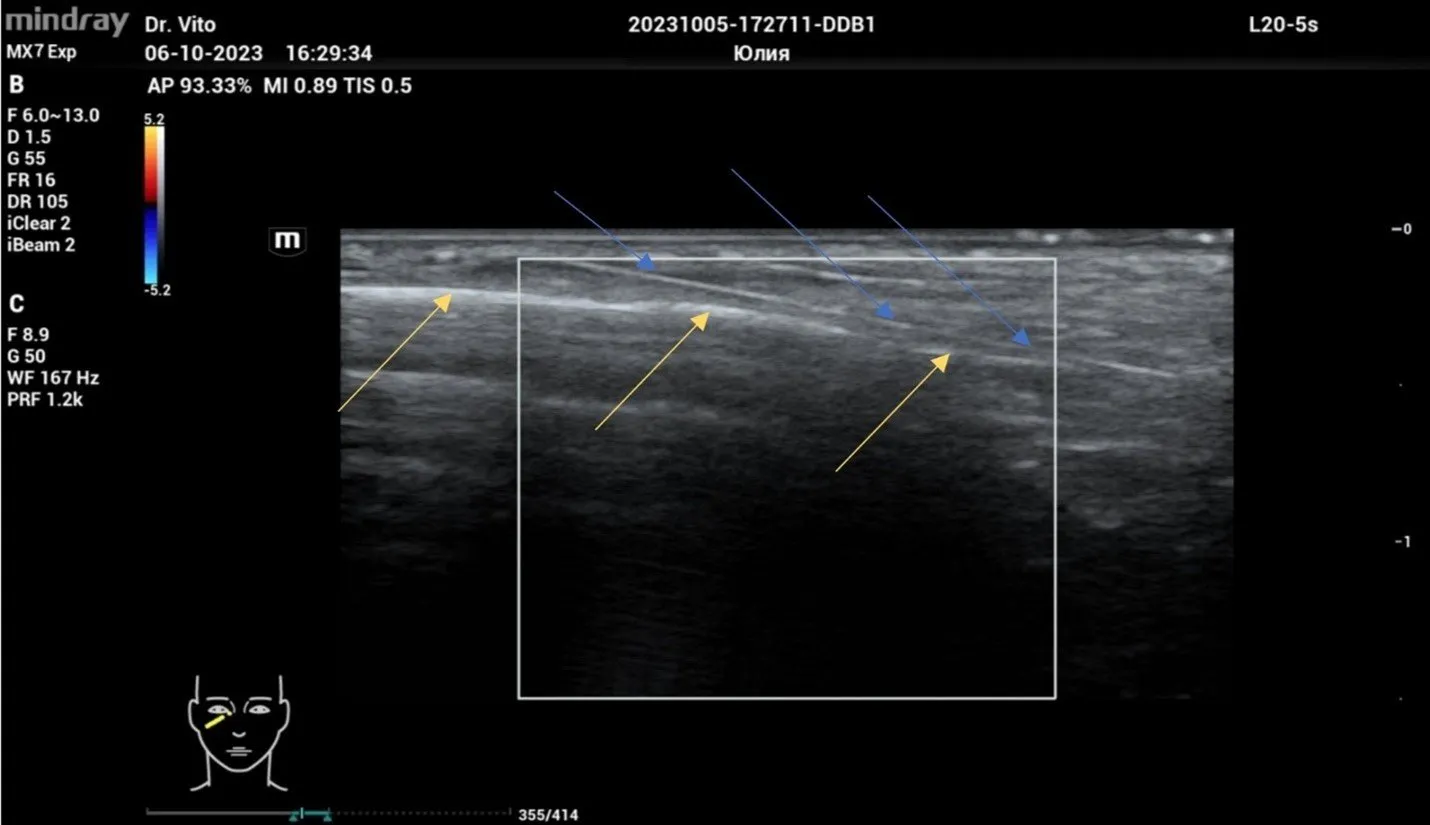

На серии УЗ-снимков хорошо визуализируется канюля 25G * 50 мм, которая находится в слое между орбитальной септой и круговой мышцей глаза над надкостницей края орбиты, что является оптимальной топографией для введения филлера и получения максимально эффективного результата. Стоит отметить абсолютную безопасность коррекции филлеров ввиду визуализации всех крупных сосудистых образований, которые легко обойти канюлей без травматизации и риска эмболии.

Рисунок 1. Синими стрелками обозначена визуализация канюли 25G * 50 мм. Желтыми стрелками обозначена надкостница.